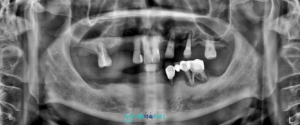

정밀 진단을 위해

파노라마 촬영을 진행한 결과,

아래턱 잔존 치아 주변의 잇몸뼈가

많이 감소하여 치아를 지지하기

어려운 상태로 확인되었고,

발치가 필요한 상황이었습니다.